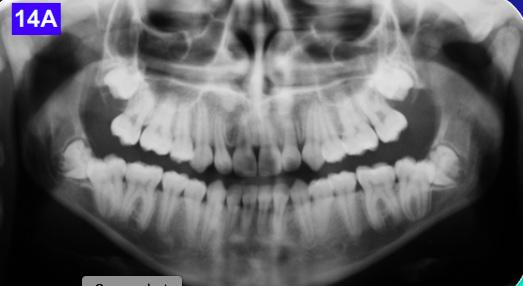

Panoramic radiogram revealed a late mixed dentition with un-erupted wisdom teeth and second molars. A significant finding was noted in that the maxillary cuspids were in transposition with the lateral incisors. There was excellent bone support and no sign of periodontal or peri-apical pathology (Figure 2-A).

Figure 2A: Pre-treatment, Panoramic radiogram Figure 2B: Pre-treatment, lateral Cephalometric radiogram

Please view the post-treatment images at the time of insertion of the retainers (Figure 14 - A, B, C. D, E, F, G, H, I, J, K, L, M, N).9

Figure 14A: Post-treatment, panoramic radiogram